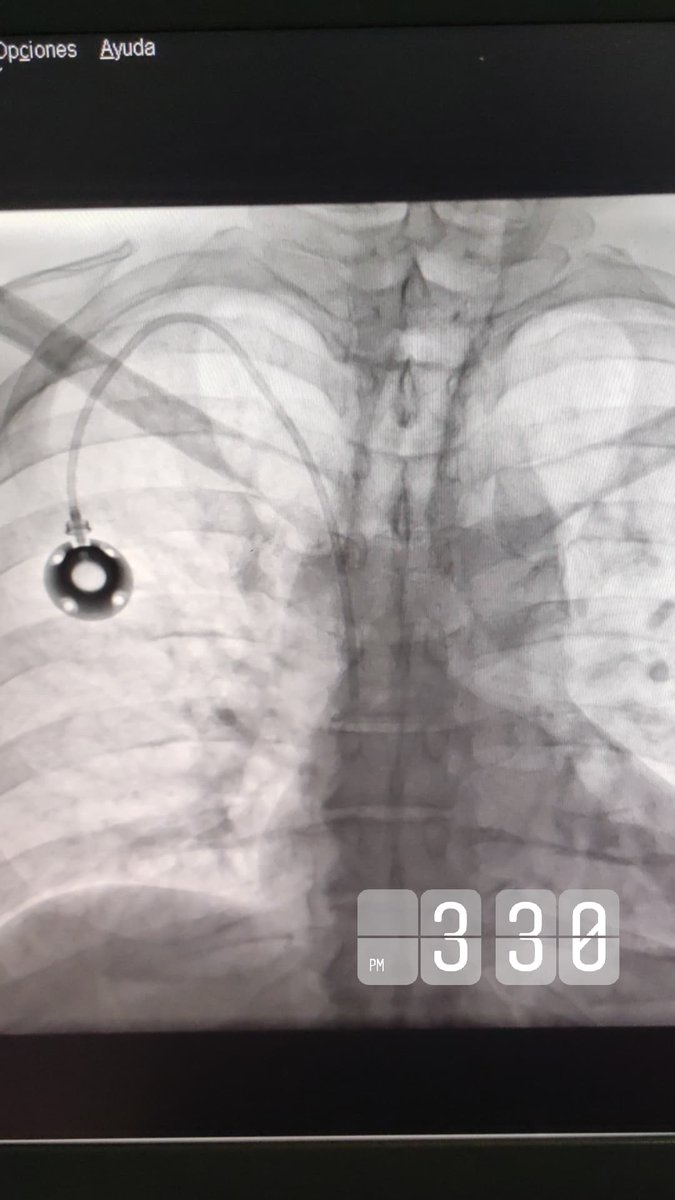

Superior mesenteric vein access for portal vein recanalization - Transjugular Intrahepatic Portosystemic Shunt in Chronic Portal Vein Thrombosis PAIRS PAIRS Society of Interventional Radiology CIRSE JVIR The Arab Journal of Interventional Radiology #irad #interventionalradiology #radiologia #mexico #tips